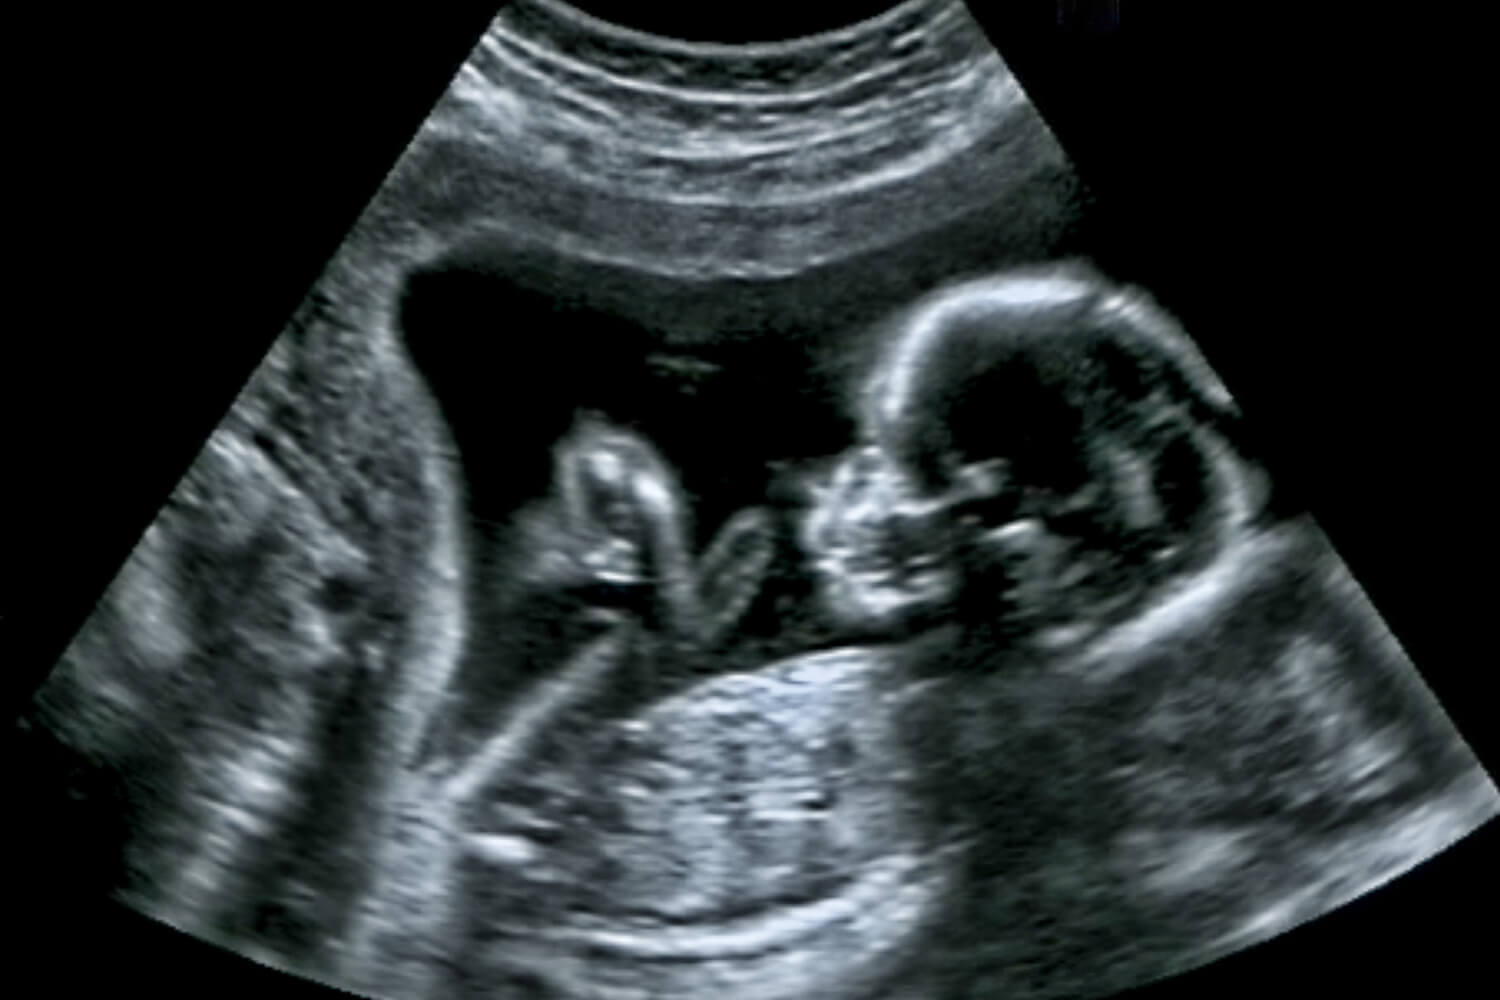

Tiffa 3D Scan Cost . The sonographer checks the baby's anatomy and examines any structural problem from head to toe. The scan can measure the size and weight of the fetus. Tiffa scan centre is an institution specialising in performing all pregnancy screening necessary for monitoring the condition of a developing foetus. The aim of this scan is to provide accurate diagnostic information for the delivery of optimised antenatal care; The anomaly scan or the tiffa scan examines the fetus from head to toe monitoring the overall growth, development, and health. The anomaly scan, is also referred to as a tiffa (targeted imaging for fetal anomalies), target or level ii scan. Learn about tiffa scan (targeted imaging for fetal anomalies), its uses, test results, procedures, and normal range during pregnancy. A tiffa (targeted imaging for fetal anomalies) scan, also known as an anomaly scan, is typically performed during the second trimester of. It is the most important scan during the second trimester.

Tiffa 3D Scan Cost Learn about tiffa scan (targeted imaging for fetal anomalies), its uses, test results, procedures, and normal range during pregnancy. The anomaly scan or the tiffa scan examines the fetus from head to toe monitoring the overall growth, development, and health. A tiffa (targeted imaging for fetal anomalies) scan, also known as an anomaly scan, is typically performed during the second trimester of. The sonographer checks the baby's anatomy and examines any structural problem from head to toe. The aim of this scan is to provide accurate diagnostic information for the delivery of optimised antenatal care; Tiffa scan centre is an institution specialising in performing all pregnancy screening necessary for monitoring the condition of a developing foetus. The anomaly scan, is also referred to as a tiffa (targeted imaging for fetal anomalies), target or level ii scan. Learn about tiffa scan (targeted imaging for fetal anomalies), its uses, test results, procedures, and normal range during pregnancy. It is the most important scan during the second trimester. The scan can measure the size and weight of the fetus.